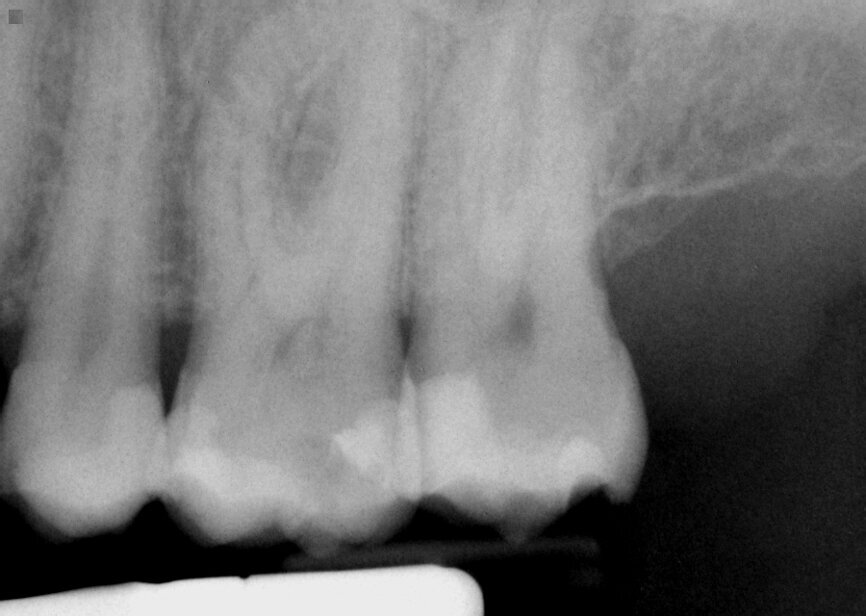

Fig. 10: Tooth 7 presented with large portion of the MBLI missing on tooth with pulpal involvement as evidenced by a moderate periapical area.

A 76-year-old female patient presented with pain on teeth 7 (maxillary right lateral incisor) and 11 (maxillary left canine). Clinical exam noted coronal breakdown of both teeth without any discernable mobility. Radiographs were taken, and it was noted that tooth 7 presented with periapical pathology and caries connection with the pulp (Fig. 10). Tooth 11 did not present with periapical pathology, but pulpal exposure was noted clinically (Fig. 11). The plan recommended was endodontic treatment of both teeth followed by restoration with a fiber post, resin core and full-coverage crown.